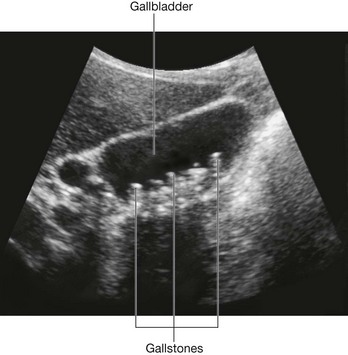

Other approaches use much smaller incisions. With the advent of small cameras and the development of minimal access surgery, tiny incisions can be made in the anterior abdominal wall and cameras inserted. The peritoneal cavity is “inflated” with carbon dioxide to increase the space in which the procedure is performed. Further instruments may be inserted through small portholes, and procedures such as cholecystectomy (removal of the gallbladder) and appendectomy (removal of the appendix) can be carried out, allowing the patient to return home sooner than a large abdominal incision would allow.